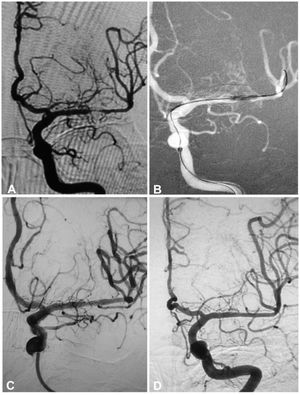

A 64-year-old man had an atherosclerotic stenosis (75%) at the M1 segment of the right middle cerebral artery treated with angioplasty and stenting of the Low-Profile Visualized Intraluminal Support (LVIS) stent. (A) The stenosis was shown at the M1 segment. (B) A balloon was used to dilate the stenosis before stenting. (C) At the end of the stenting with a LVIS stent (3.5mm×15mm), the stenotic segment was almost restored to the normal diameter. (D) At 6-month follow-up, the stented segment of artery remained totally open with slight instent stenosis.